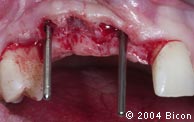

27. | 用平行杆确定经先锋钻预备的牙槽窝的位置方向。 |

30. | 就位的引导杆显示三颗种植体的位置方向。 |